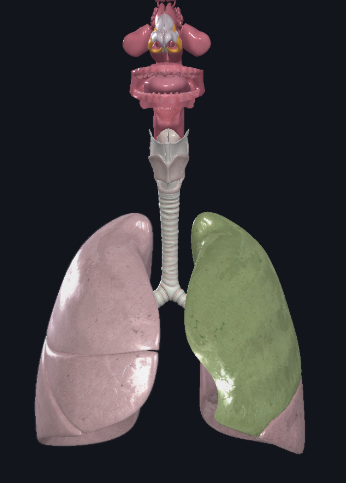

What structure is this?

Cardiac Notch

What structure is this?

Superior lobe of the left lung

What structure is this?

Inferior lobe of the left lung

What structure is this?

Left lung